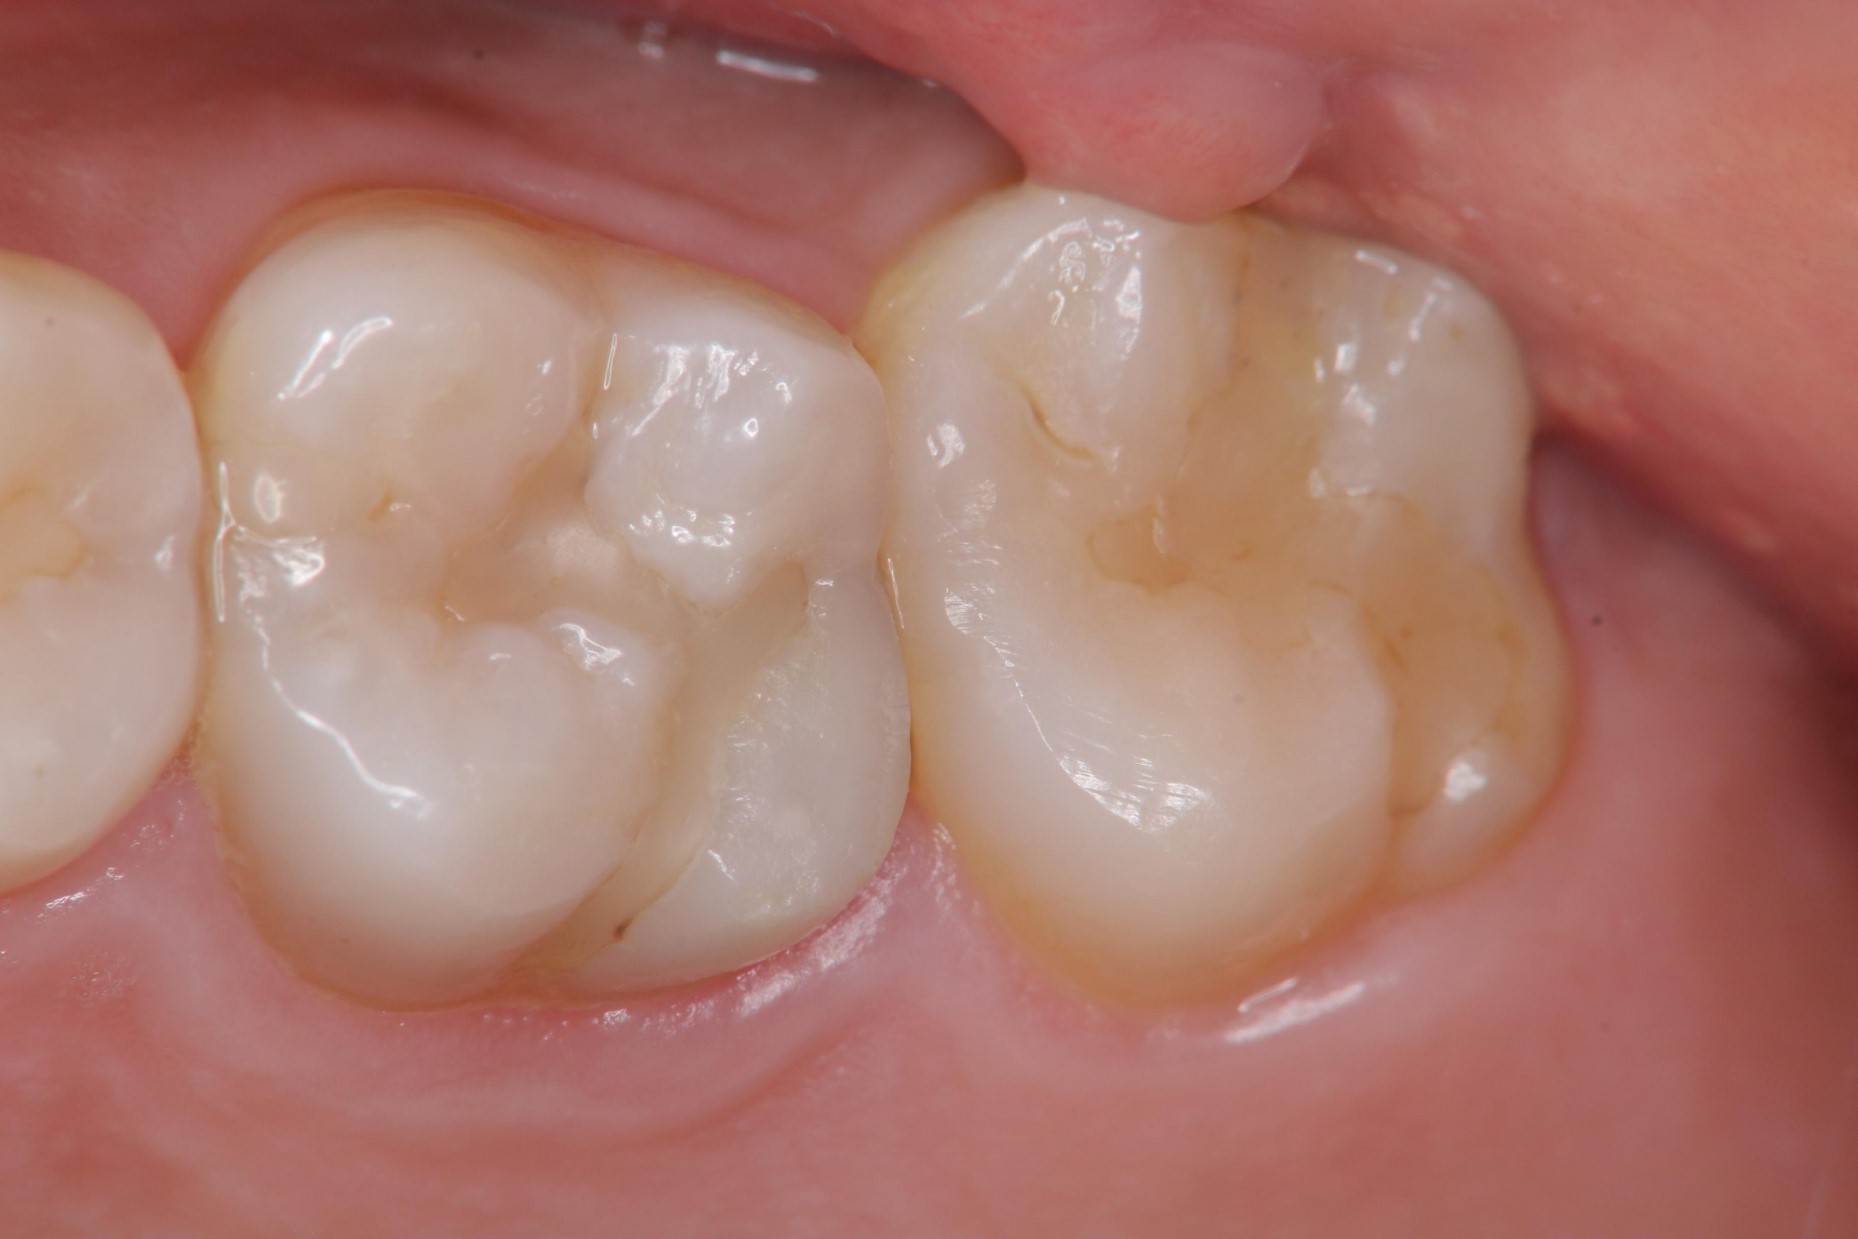

治療前,二次蛀牙